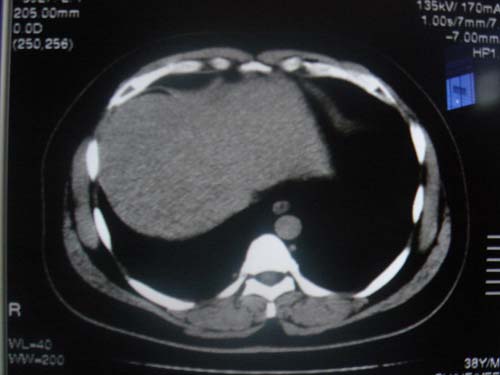

患者 男 40 右上腹不适 有胆囊息肉病史2年

最后二副图像示胆囊壁增厚,与肝分界欠清,建议强化ct或磁共振

片中示肝脏的ct值低于脾脏,肝脏右叶外缘部份凹凸不平,考虑脂肪肝,肝硬化可能。结合其检查如b超或ct增强检查。

肝右叶密度不均,脾大。强烈要求增强扫描除外浸润型肝癌。

肝大   密度降低  脾大  脂肪肝?